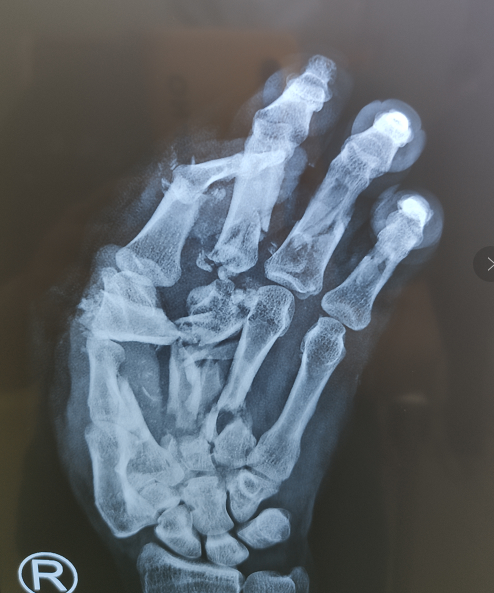

经检查发现,刘师傅右手多段离断,掌指骨碎成了十多块,肌腱、血管、神经多段离断伴缺损。

术中李医生手术团队为刘师傅把一根一根钛克氏针扎在他的手上进行骨折关节复位,一根,两根......直到21根,触目惊心,然后依次吻接受伤的血管、神经和肌腱,最终经过了六个多小时,手术顺利完成,刘师傅安返病房。